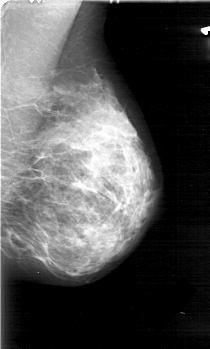

D_4031_1.RIGHT_MLO

RIGHT_MLO LINES 5176 PIXELS_PER_LINE 3001 BITS_PER_PIXEL 12 RESOLUTION 43.5 OVERLAY